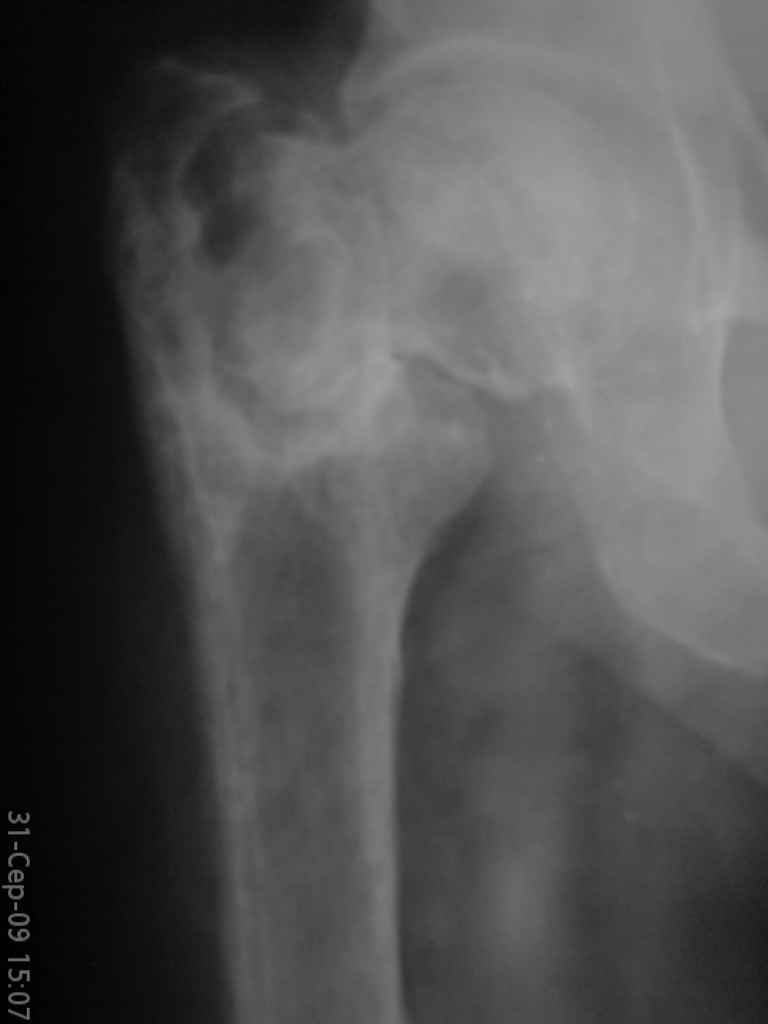

Больная, 62 года,жалуется на боли,неопорность левой ноги. Ходит с помощью костылей, укорочение ноги 3 см. Два года назад была оперирована кокой-то накостной пластиной, пластину удалили 4 мес назад. Вопрос такой: предлагать эндопротезирование или делать МОС (что-то по типу стержня Gamma)?

За качество снимков извините, по данным МРТ - головка живая